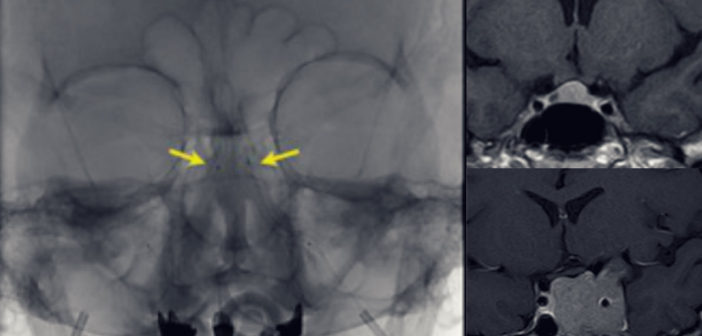

El especialista de la Clínica Alemana vislumbra diversos desafíos para esta patología. Entre ellos, aquellos adenomas corticotropos muy pequeños que no se logran identificar con estudios de resonancia convencionales y relata que en el Instituto de Neurocirugía se está desarrollando un protocolo de resonancia magnética modificado que podría aumentar la pesquisa de la lesión antes de la operación. Otro desafío son los tumores funcionantes invasores al seno cavernoso, que no son susceptibles de llevar a remisión con la cirugía.